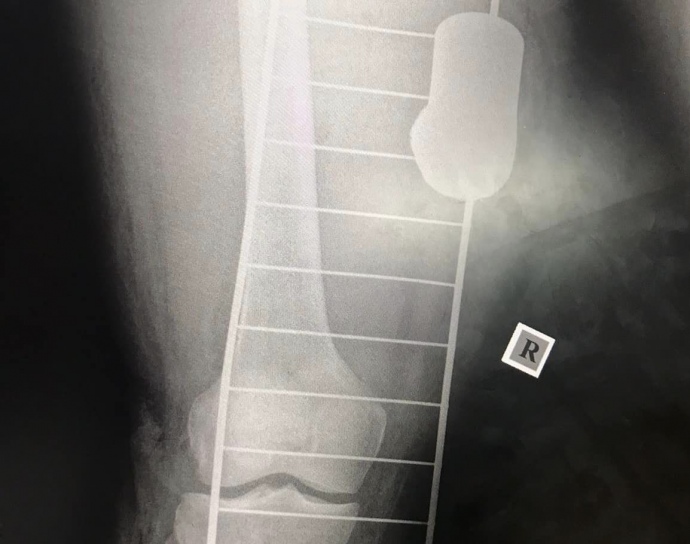

Doctors at a field hospital in Ukraine have removed an unknown type of submunition from the leg of a wounded Ukrainian defender.

The submunition is the warhead of a cluster munition. An X-ray showed that it hit the soldier's thigh. The length of the submunition is approximately half the length of the doctor's palm.

The Medical Forces noted that the soldier also has a fracture and related complications. Despite this, doctors managed to save the limb.